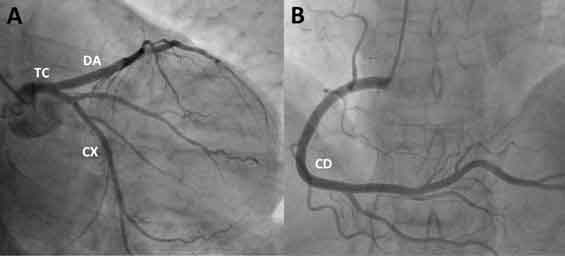

Angiografía coronaria (Coronariografía)

Estudio que se realiza en un laboratorio de cateterización cardiaca

Tras administrar un calmante para relajar al paciente se inyecta un colorante en la corriente sanguínea para producir una radiografía “animada” de la actividad del corazón y del flujo de sangre a través de las válvulas cardiacas y arterias coronarias (coronariografía). La coronariografía nos muestra cuantas obstrucciones hay y su gravedad. Este estudio nos sirve para determinar cuál sería el tratamiento más eficaz de la insuficiencia coronaria.